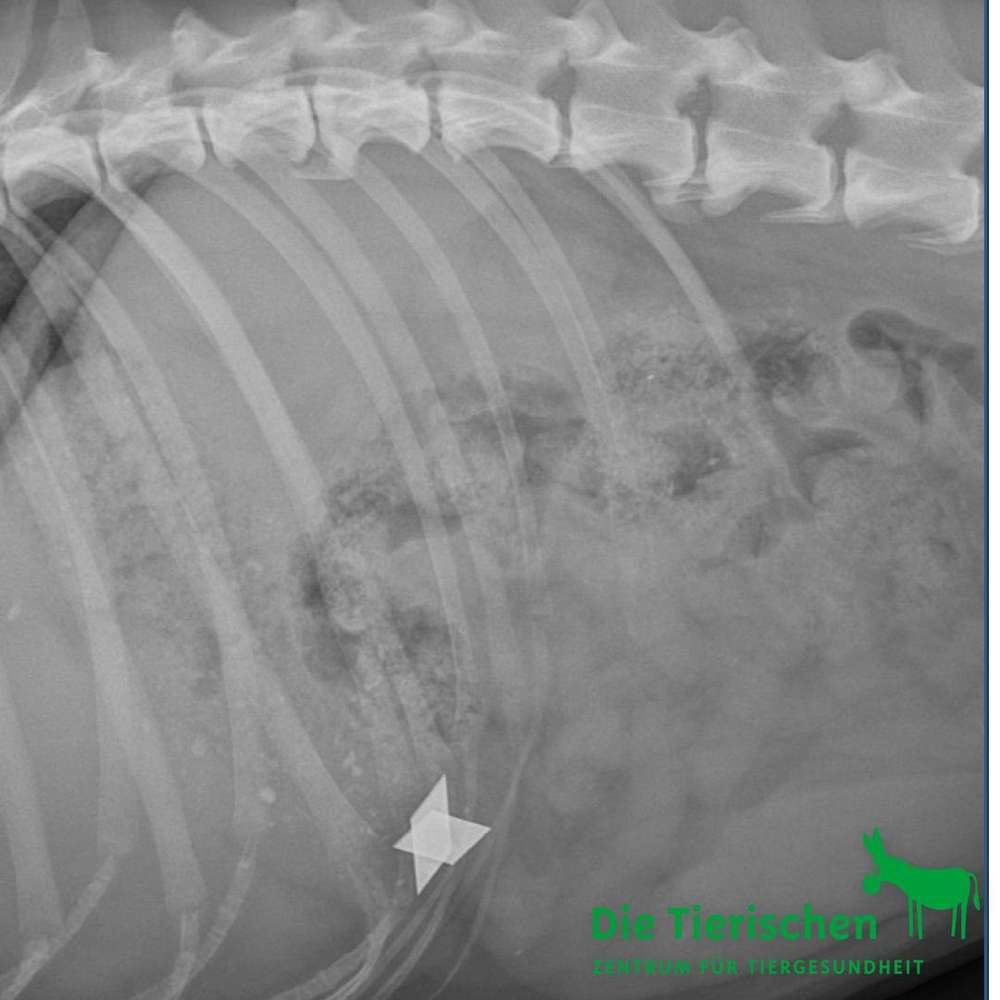

‼️Im Umkreis Baiersdorf/ Wellerstadt & Langensendelbach/ Bräuningshof wurden gestern in Leberwurst versteckte Cuttermesserklingen über den Zaun geworfen. Gestern hatten wir einen Hund hier, dem das passiert ist. Dieser wurde operiert und es geht ihm gut. So etwas kann aber auch anders ausgehen. Bitte passt gut auf eure Hunde auf! So etwas kann sehr schnell lebensgefährlich werden und zum Tot führen.